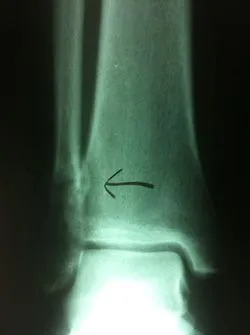

Stress fractures are often a clinical diagnosis as x-rays may be negative initially. The patient would typically experience pain and swelling across the top of the metatarsals. The pain would be mild in the morning. However, would get worse with weight-bearing. When x-rays are negative these problems are still treated as a fracture. X-rays taken 14-21 days after the injury will often show healing of the stress fracture by bone callus along the shaft of the bone.

Stress fractures that occur towards the end of the bone in the metaphyseal region often go nondisplaced after the healing process.

Stress fractures that occur in the midportion of the metatarsal can displace up, causing the potential for future problems in the metatarsal head region.